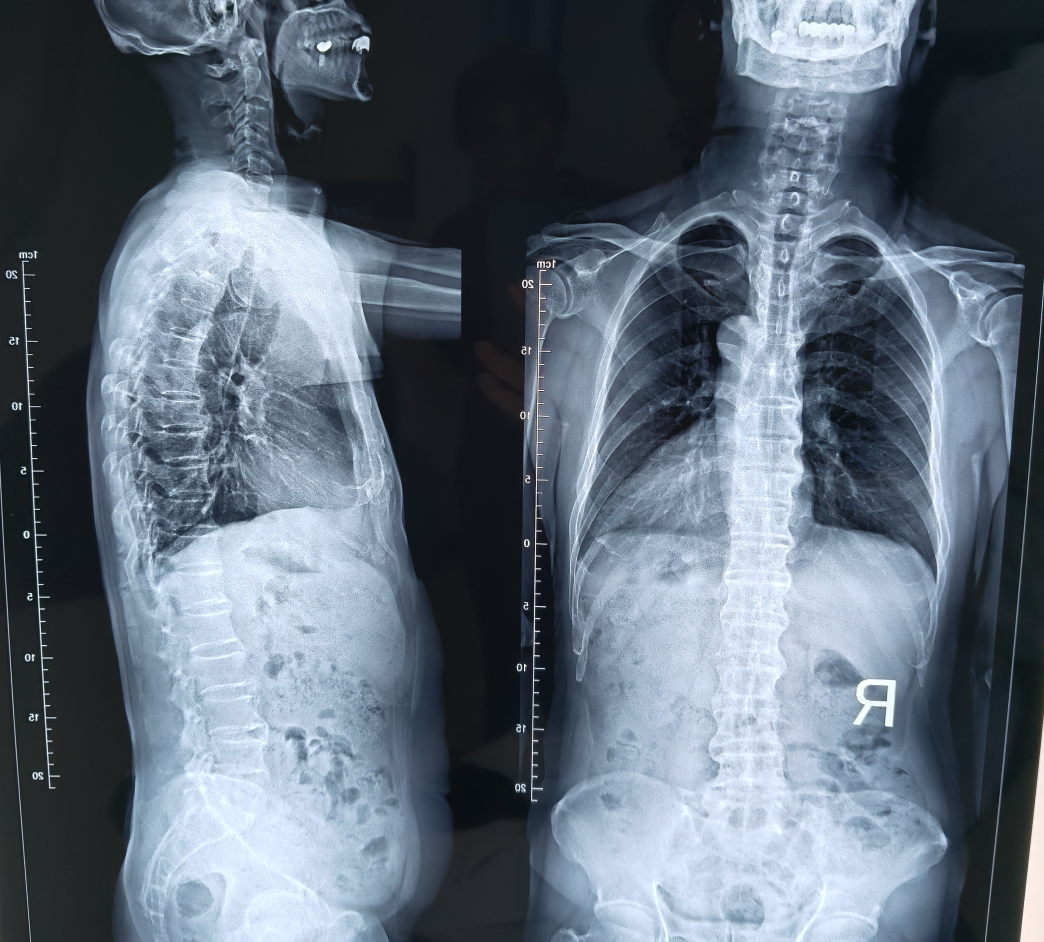

接诊医生查体发现王先生腰背部可触及明显骨性凸起,脊柱X线片显示:脊柱部分前纵韧带骨化,椎小关节面毛糙、硬化,部分关节融合;多椎体前缘骨质增生、变尖;双侧骶髂关节边缘骨质增生,关节间隙变窄,部分消失。结合影像学及临床表现,诊断为强直性脊柱炎,目前已重新启动生物制剂治疗,症状明显得到了缓解。

图1

图2